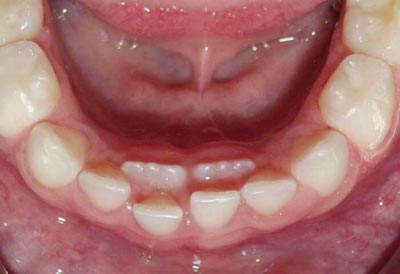

Stalni zub raste iza mlečnog najčešće u slučaju donjih jedinica. To se javlja najčešće zato što je zametak stalnog zuba blago pomeren ka usnoj duplji u odnosu na mlečni zub. U toj situaciji stalni zub prilikom rasta ne apsorbuje pravilno koren, već apsorbuje samo njegovu unutrašnju polovinu, pa se mlečni zub ne rasklati kako treba.

Ovo se može desiti i kod četvorki i petica. Mlečni zubi četvorke i petice su molari (kutnjaci), a stalni zubi četvorke i petice su premolari (kutnjaci su kod stalnih od šestice). Stalna četvorka premolar može biti ista ili manja od mlečnog molara četvorke. Ukoliko je manja, ona često ne može da u potpunosti apsorbuje koren, pa zub kreće da raste pored mlečnog zuba.

Sve ovo su relativno česte i normalne pojave. Međutim, ukoliko se ne reaguje na vreme, nakon smene zuba zubi neće biti poravnati u savršen ziz, već će biti krivi.